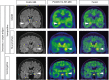

Autoimmune limbic encephalitis (ALE) presents with new-onset mesial temporal lobe seizures, progressive memory disturbance, and other behavioral and cognitive changes. CD8 T cells are considered to play a key role in those cases where autoantibodies (ABs) target intracellular antigens or no ABs were found. Assessment of such patients presents a clinical challenge, and novel noninvasive imaging biomarkers are urgently needed. Here, we demonstrate that visualization of the translocator protein (TSPO) with [18F]DPA-714-PET-MRI reveals pronounced microglia activation and reactive gliosis in the hippocampus and amygdala of patients suspected with CD8 T cell ALE, which correlates with FLAIR-MRI and EEG alterations. Back-translation into a preclinical mouse model of neuronal antigen-specific CD8 T cell-mediated ALE allowed us to corroborate our preliminary clinical findings. These translational data underline the potential of [18F]DPA-714-PET-MRI as a clinical molecular imaging method for the direct assessment of innate immunity in CD8 T cell-mediated ALE.